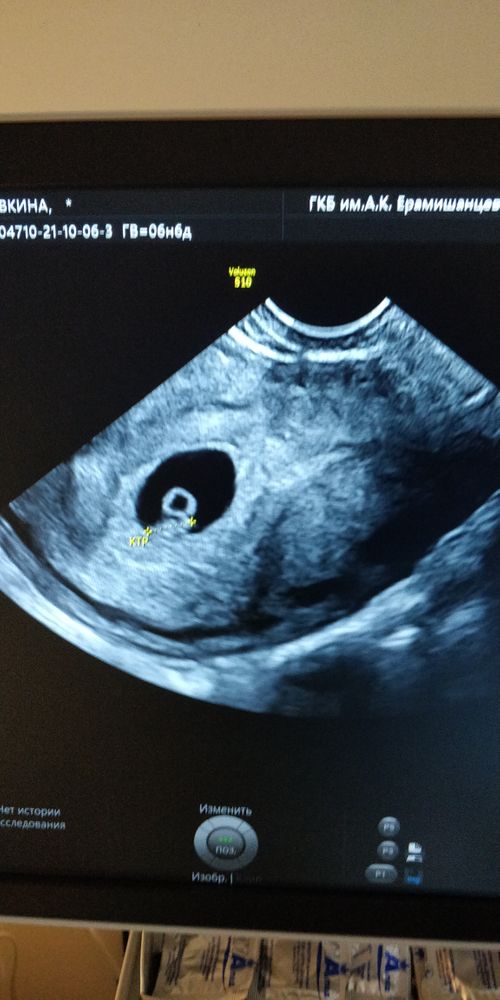

УЗИ, КТГ, доплерВ общем после ЗБ,я нервничаю очень ,но вот сегодня была на УЗИ по мес.6+6 а по КТР 6+4

💓СБ 129 ,на учёт меня так и не поставили ,на этот раз врач заболела)))Теперь 15.10 идти вставать на учёт,и наконец то назначат скрин🤟